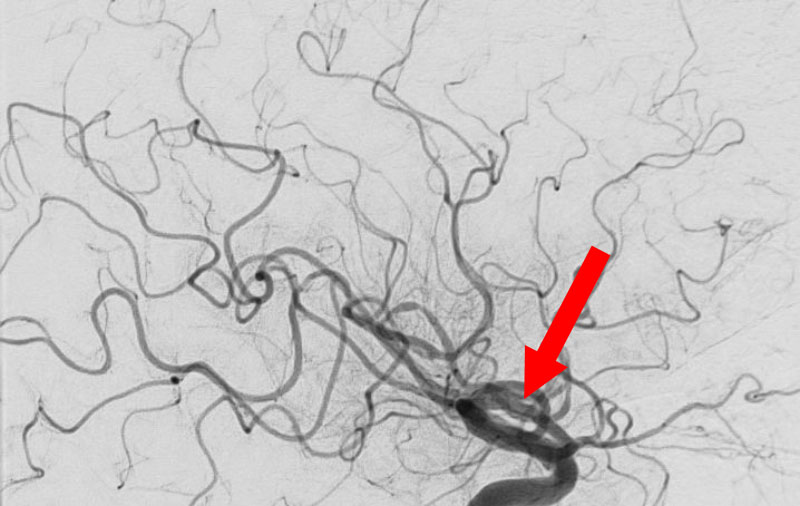

No.1591 手術前

No.1591 手術中

No.1591 手術後

'25年10月

硬膜動静脈瘻

50代

救急外来